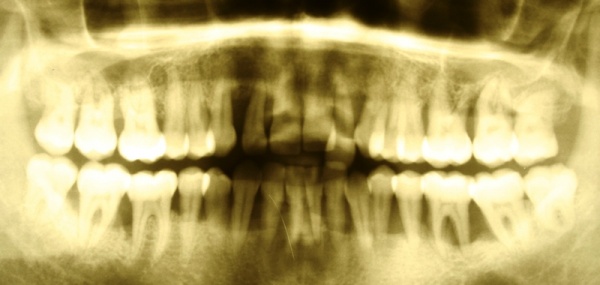

[Abb-2]In den vergangenen zehn Jahren wurden circa 34.000 Implantate durch das SanABw bzw. das KdoSanDst UA III genehmigt. Wenn die von Roos-Jansacker publizierte Prävalenzrate von 6,6 % zugrunde gelegt wird, müsste zwischenzeitlich an circa 2250 Implantaten eine Periimplantitis diagnostiziert worden sein. Zitzmann et al. geben eine Rate von 28 % periimplantäre Entzündungen an. Dies bedeutet, dass circa 9500 Implantate eine Mukositis bzw. Periimplantitis aufwiesen bzw. aufweisen.

In der prächirurgischen Phase muss ein besonderes Augenmerk auf die prognostische Einschätzung der parodontalen und dentalen Situation gelegt werden. Dabei ist insbesondere auf die allgemeinmedizinische und spezielle dentale Anamnese zu achten. Bornstein et al. (2009) untersuchten den Einfluss von Allgemeinerkrankungen auf die Periimplantitis. Unter anderem Safi et al. (2009) wiesen auf die Bedeutung einer Parodontitishistorie hin. Aber auch die Lebensgewohnheiten des Patienten haben einen entscheidenden Einfluss (Tabakkonsum, ungenügende Mundhygiene, fehlende Nachsorge [Heitz – Mayfield & Huynh – Ba 2009]) (Abb. 3).

Diagnostische Parameter für die Beurteilung der dentalen und der periimplantären Zustände sind die Plaqueakkumulation, die Sondierungstiefen des Zahnes und des Implantates, Bluten auf Sondierung, Suppuration und der radiographische Knochenverlust (Salvi & Lang 2004). Unabdingbar ist im Minimum eine Sechspunktmessung (Sondiertiefen und klinischer Attachmentlevel). Immer wieder hört man von der Befürchtung, dass durch ein Sondieren des Implantates dieses geschädigt wird. In einer histomorphometrischen Studie an Hunden haben Etter et al. (2002) die Heilung des periimplantären Weichgewebes nach standardisiert klinischem Sondieren untersucht. Die Heilung des Epithelansatzes nach Sondierung des gesunden periimplantären Gewebes ist nach fünf Tagen abgeschlossen. Erfahrungsgemäß ist bei besonders aufmerksamem und vorsichtigem Sondieren ein äußerst geringes Verletzungsrisiko gegeben. Auch diese Techniken können in einem Praktikum bei einem Parodontologen aufgefrischt werden.

Im Rahmen einer solchen Nachuntersuchung werden neben der Plaqueakkumulation die klinischen Parameter Sondiertiefe und klinischer Attachmentlevel (6-fach je Zahn / Implantat), Bluten nach Sondieren (BnS), Suppuration und gegebenenfalls der radiographische Knochenverlust (Salvi & Lang 2004) erfasst.